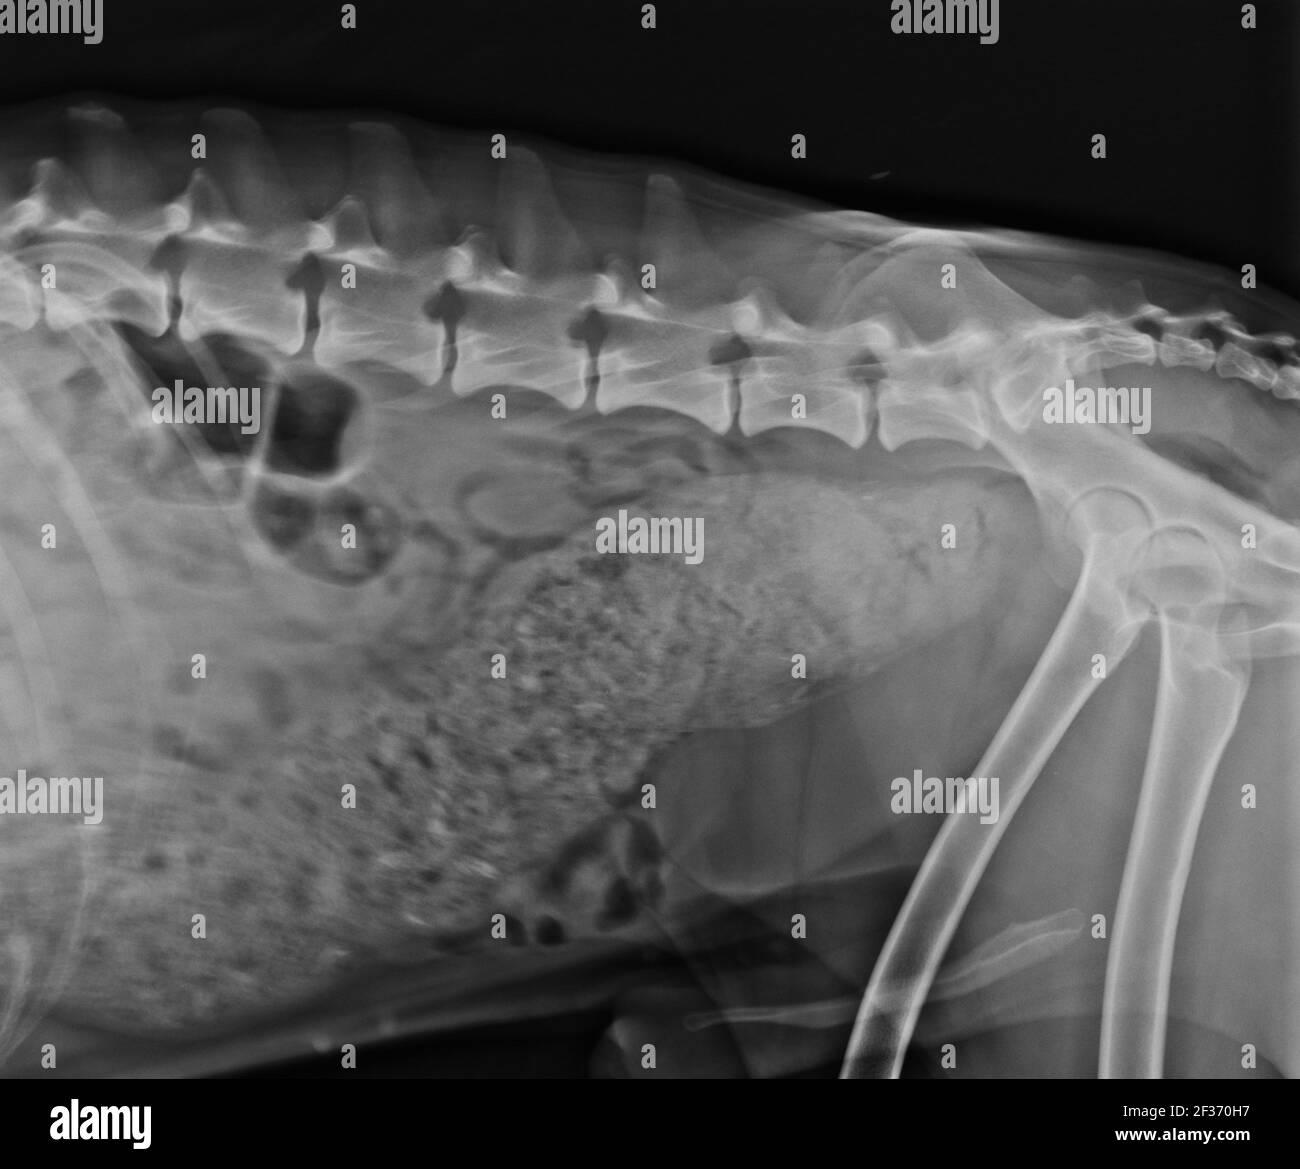

From www.bigstockphoto.com

Xray Dog Lateral View Image & Photo (Free Trial) Bigstock Dog Constipation X Ray Management can be surgical or with medication, depending on severity. Other tests may be needed in cases of longterm constipation or obstipation. Difficulty in passing stool can mean extra effort (constipation) or complete impossibility (obstipation). Radiopaque foreign bodies of the stomach are usually easily identified. If your veterinarian suspects your dog is constipated, they will start with a physical and. Dog Constipation X Ray.